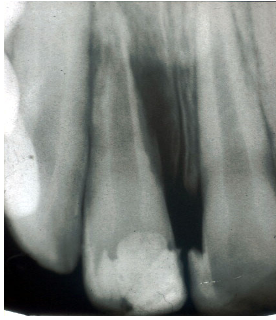

Patient is 10/11 years old and they had extrusion of their 11. Radiograph of 11 given, describe what you see, give a diagnosis and mention how you manage this (3 marks)

A

Periapical Radiolucency

Tramlines of RC intact

Widened PDL space

Loss of Lamina dura

External inflammatory root resorption- When the pulp is necrotic causing damage to the PDL (necrotic pulp tissues and toxins are reaching the external surface via dentinal tubules)

Treatment:

Remove cause of inflammation:

RCT with NS CaOh 4-6 weeks then obturate .

RCT( Pulp extirpate+ Mechanical debridement+ irrigation +NS CaOH 4-6 weeks then obturate)